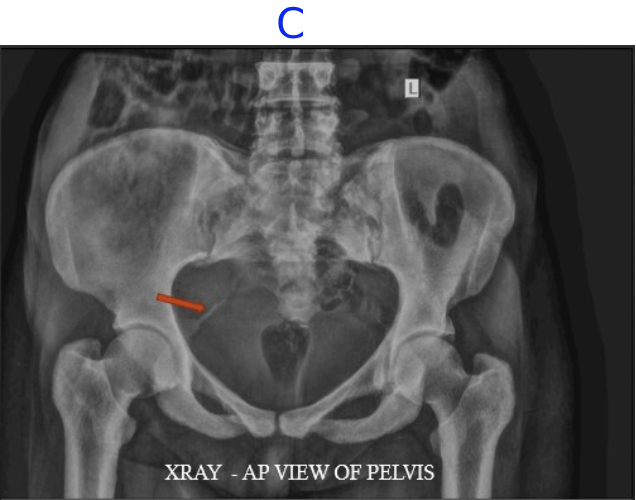

C) LEGENDS

• Diffusely increased density of the bones.

• Calcification of the right sacrospinous ligament.